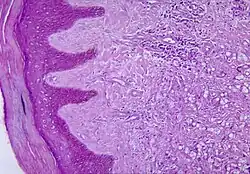

Lobomykoza (ang. Lobo’s disease, lobomycosis, lacaziosis) – przewlekłe zakażenie ograniczone do skóry, wywołane przez grzyb Paracoccidioides loboi (wcześniej nazywany Loboa loboi)[1]. Po raz pierwszy jednostka chorobowa została opisana przez Jorge Lobo w 1939 (stąd inna nazwa, choroba Lobo). Wśród rdzennych mieszkańców Amazonii znana była wcześniej pod nazwami miraip i piraip.

Grzyb dostaje się do organizmu przez uszkodzone powłoki ciała, rozwija się in situ przez nieokreślony czas, po czym atakuje tkankę podskórną. Pierwszą zmianą jest brodawka lub mała grudka. Liczba guzków powiększa się, guzki rosną i zlewają się, w wyniku czego powstaje guzowata zmiana chorobowa. Zakażenie może szerzyć się drogą naczyń chłonnych, zwłaszcza u osób starszych. Niektóre guzki mogą mieć przetoki, przez które wydostaje się masłowata wydzielina, zawierająca duże ilości komórek grzyba. Mogą pojawiać się owrzodzenia. Lobomyces kolonizuje skórę w najchłodniejszych okolicach ciała: na kończynach, policzkach i pośladkach. Chorują najczęściej mężczyźni w wieku 30–40 lat, starsi rzadziej, a kobiety 7-9 razy rzadziej. Choroba rzadko występuje u dzieci i młodzieży. Dotychczas opisano kilkaset przypadków, większość z nich dotyczyła osób pozostających w częstym kontakcie z wodą (górnicy, rybacy, zbieracze kauczuku lub orzechów itp.). Większość znanych przypadków pochodzi z terenu Amazonii, Brazylii i Surinamu. Zachorowania stwierdzono w Kolumbii, Wenezueli, Kostaryce, Panamie, Meksyku i Gujanie Francuskiej.